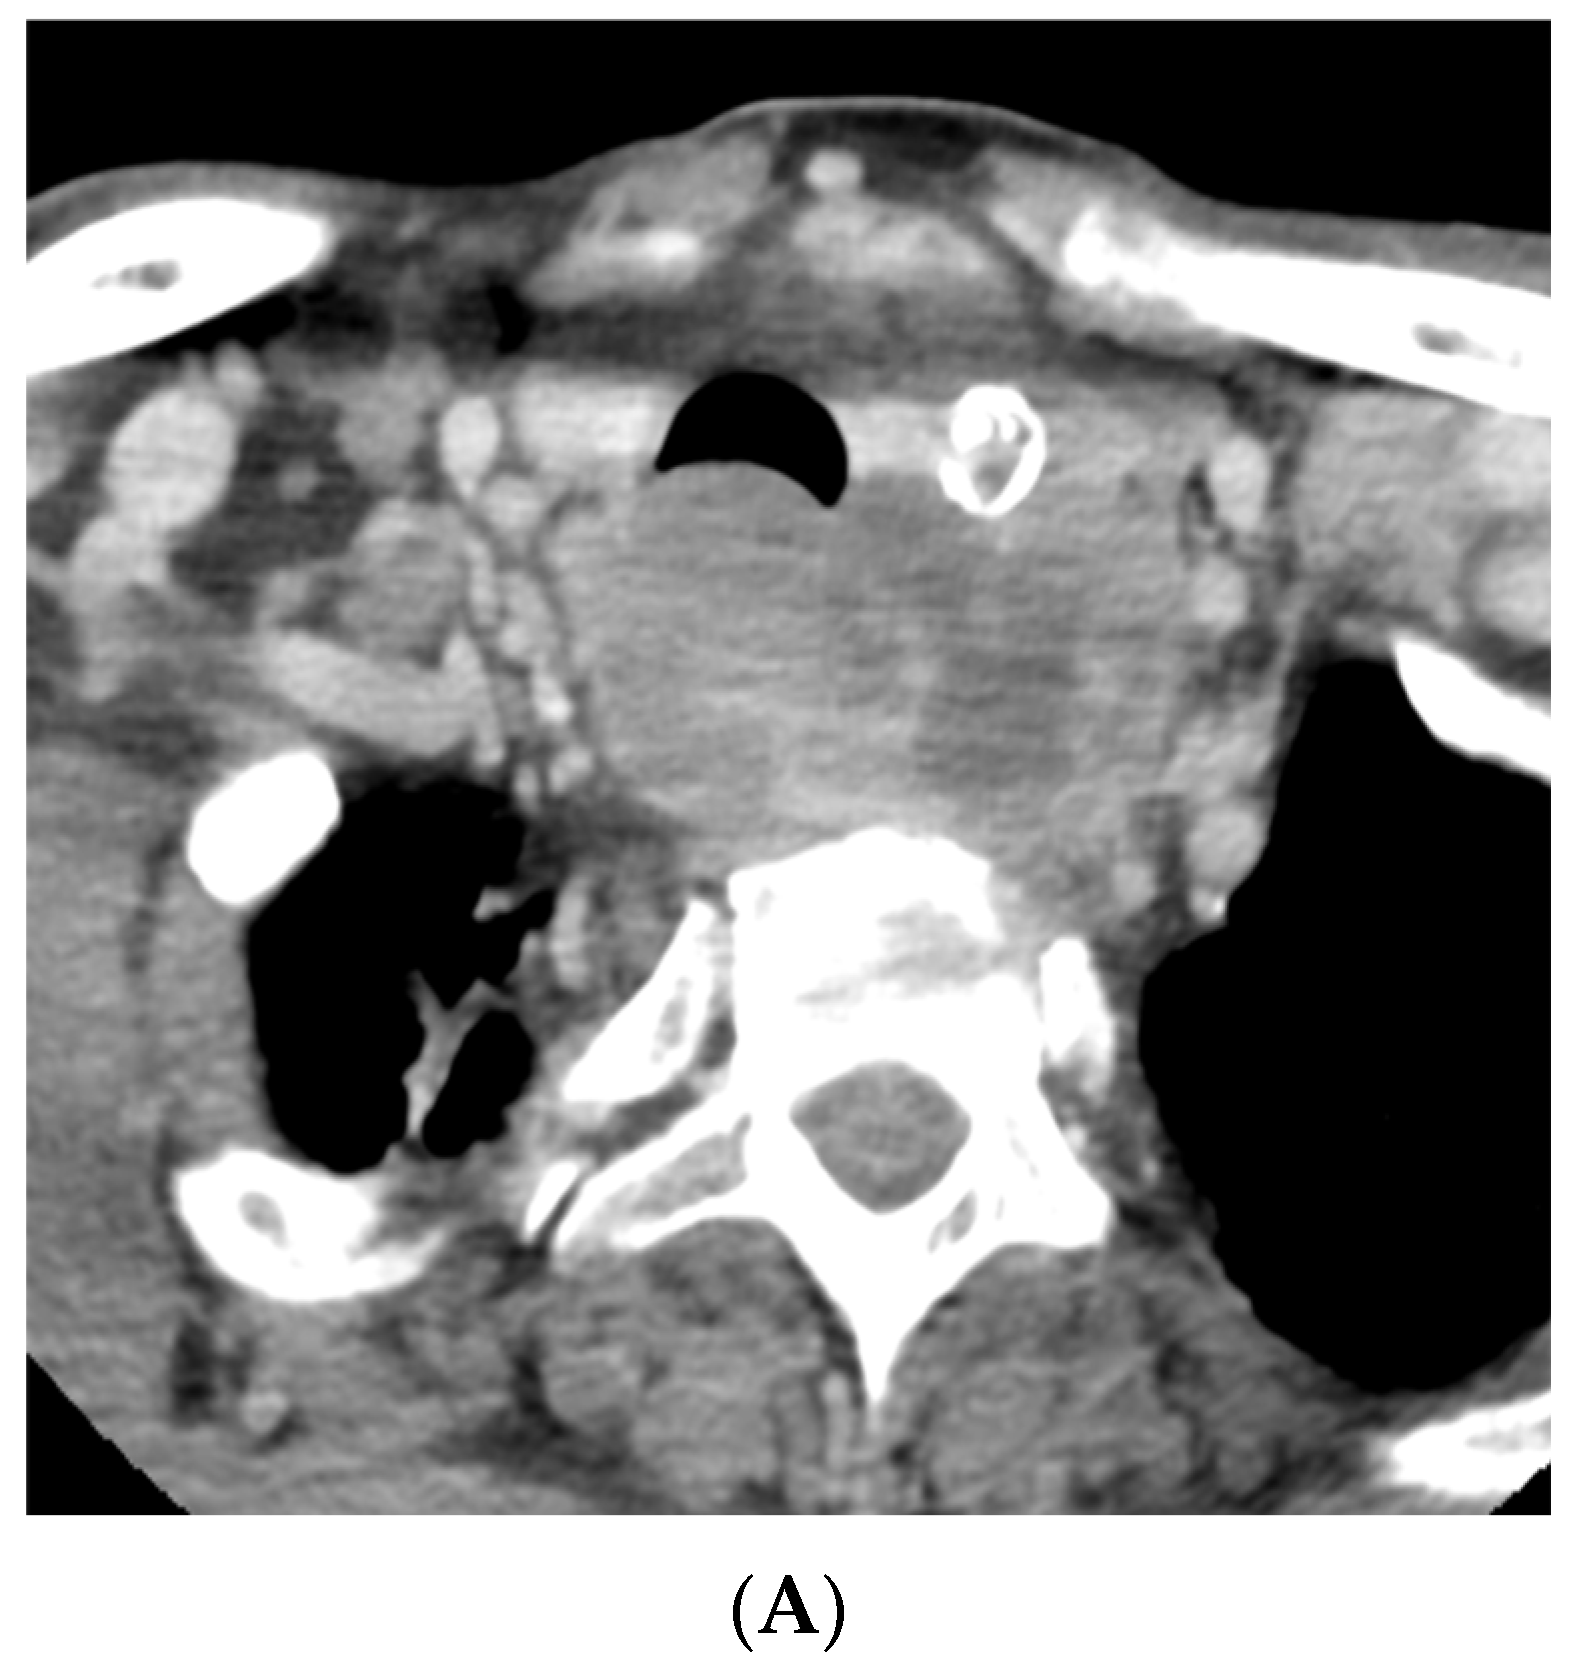

As outlined by the accompanying patient testimony, a 65-year-old gentleman presented with a 6-week history of dysphagia. Computed tomography (CT) imaging of the thorax, abdomen, and pelvis, and magnetic resonance imaging (MRI) of the neck revealed a 7.2 centimeter (cm) mass centered in the left lobe of the thyroid. The mass involved the cervical esophagus and posterior tracheal wall, leading to moderate cervical tracheal airway narrowing and invasion of both the prevertebral fascia and the posterior arch of the cricoid with metastatic right level 2, bilateral level 3, and bilateral level 4 neck nodes (shown in Figure 1 and Figure 2). A 12 millimeter (mm) right hilar node and right paratracheal and subcarinal nodes of less than 10 mm were suspicious for malignant involvement (Stage IVC) [13].

Figure 2.

A follow-up CT of the neck and thorax performed 12 days later demonstrated a significant decrease in the hypo-enhancing (likely anaplastic) component of the mass with residual enhancing mass and adenopathy (likely papillary component) (A,B). (A) Axial image at the level of the second thoracic vertebra. (B) Axial image at the level of the sixth cervical vertebra.